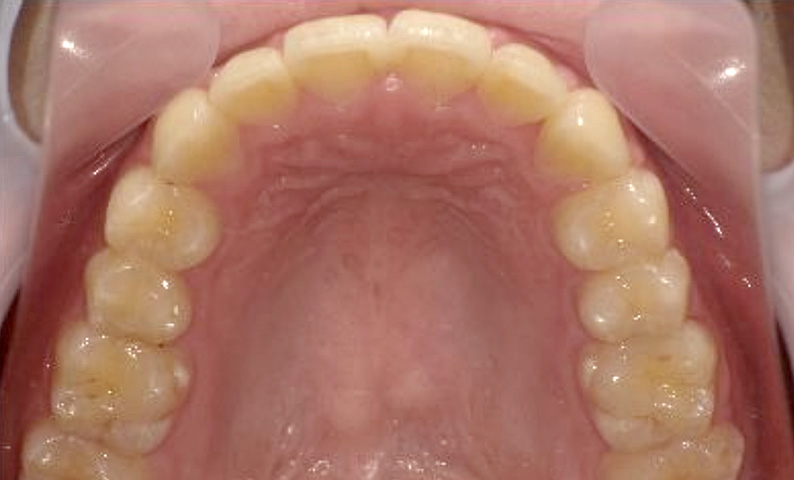

症例_025 上顎だけの部分矯正

治療期間:7ヶ月金額:30万円+税女性前歯のガタガタ上の前歯だけ

| Before | After |

|---|---|

|